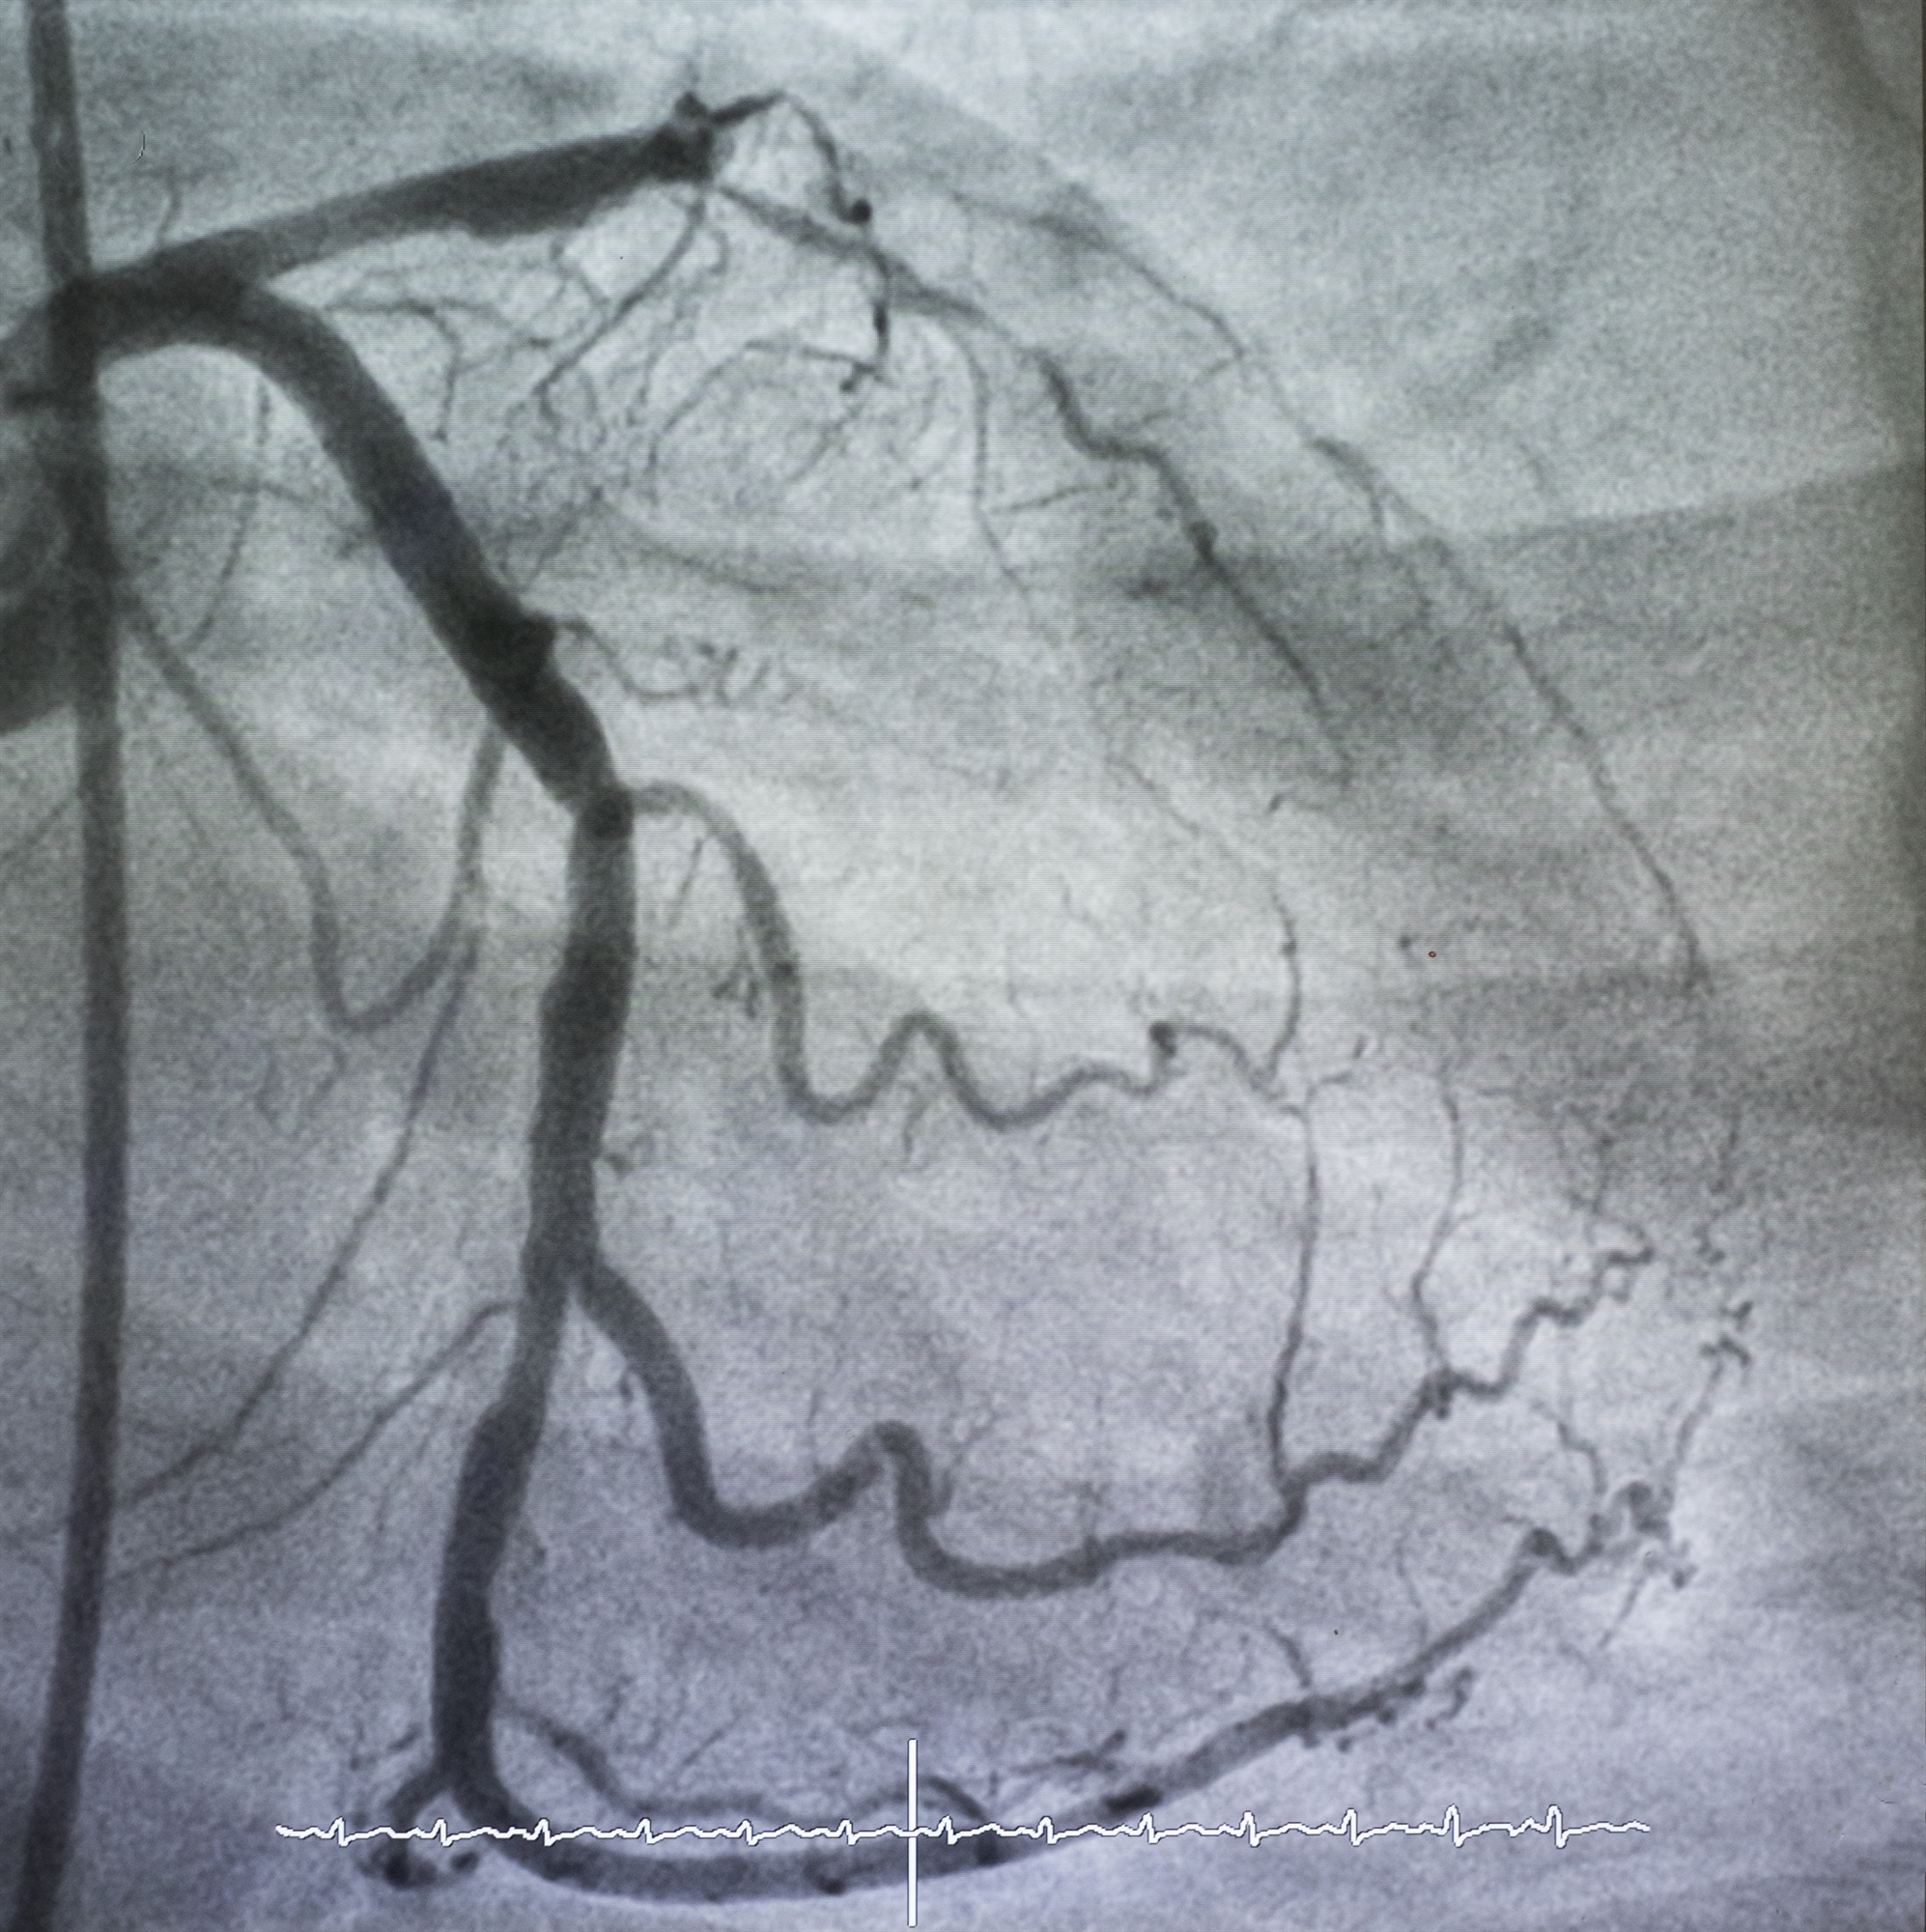

Οι γιατροί υποπτεύονται την ύπαρξη μικροαγγειακής δυσλειτουργίας σε άτομα που έχουν στηθάγχη, αλλά χωρίς ενδείξεις στένωσης των αρτηριών στη στεφανιογραφία. Η εξέταση αυτή, η οποία χρησιμοποιεί σκιαγραφικό και ακτίνες Χ, απεικονίζει μόνο το περίγραμμα του αυλού, το εσωτερικό του σωλήνα των αρτηριών (βλ. εικόνα).

«Ωστόσο, η ανάλυση δεν είναι αρκετά υψηλή ώστε να απεικονίσει τα μικρότερα αγγεία, όπου εμφανίζεται η μεγαλύτερη αντίσταση στη ροή του αίματος», λέει η δρ Viviany Taqueti, η οποία διευθύνει το Εργαστήριο Καρδιακών Δοκιμασιών Κοπώσεως στο συνεργαζόμενο με το Χάρβαρντ Brigham and Women’s Hospital.